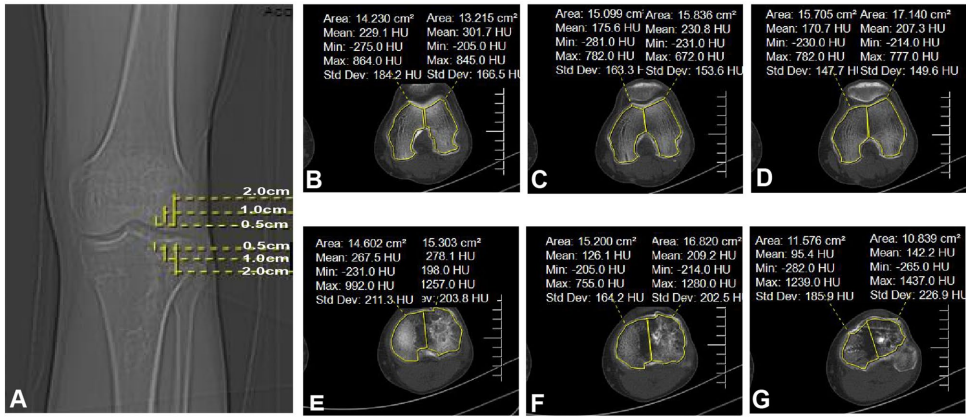

本研究针对胫骨平台骨折(TPFs)术后创伤性骨关节炎(PTOA)风险与骨密度(BMD)关联不明的临床问题,通过分析103例接受双反牵引复位微创术(MIPPO-DRTR)患者的CT骨密度(Hounsfield Units, HU)、膝关节对线参数(HKA/MPTA/LDFA/JLCA/PTS)及功能评分(SF-36/HSS),首次揭示股骨远端与胫骨近端BMD升高与膝关节功能下降、生活质量恶化及内翻畸形加重显著相关(如股骨内侧BMD与HKA负相关,r=-0.320, P=0.017),尤其对高BMI患者影响更显著。该发现为术后骨密度管理优化关节对线、延缓PTOA进展提供了新依据。

河北医科大学第三医院创伤急救中心的研究团队在《Journal of Orthopaedic Surgery and Research》发表的最新研究中,首次通过CT衍生的Hounsfield单位(HU)量化膝周骨密度,揭示了骨矿物质分布与关节畸形演化的深层联系。该研究纳入2015-2018年间103例接受MIPPO-DRTR手术的TPFs患者,平均随访7.37年,采用三大关键技术:

3. 关节对线的骨密度驱动机制

本研究首次证实:膝周骨密度异常升高是PTOA进展的独立危险因素。其机制在于: